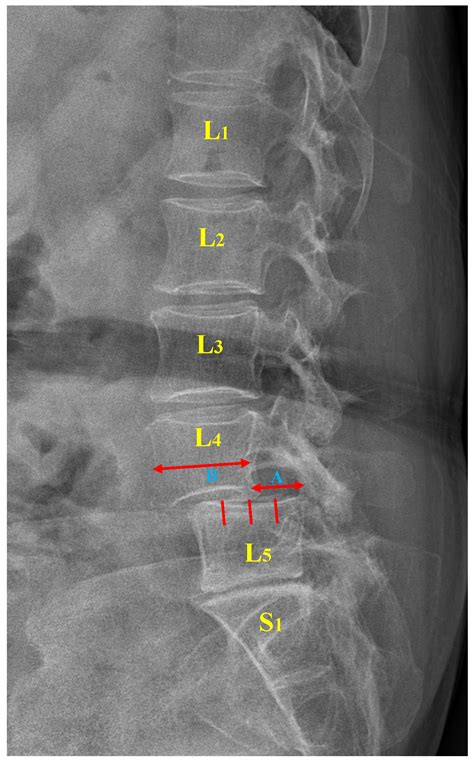

Spondylolisthesis Grade 1 is characterized by a slight forward slip of one vertebra over the one below it, typically less than 25% of the vertebral body. This condition can occur in various parts of the spine but is most commonly found in the lumbar region, particularly at the L5-S1 level. The slip can be caused by several factors, including degenerative changes, trauma, or congenital abnormalities.

Diagnosing Spondylolisthesis Grade 1

• Imaging Tests: X-rays, CT scans, and MRI scans are commonly used to visualize the spine and determine the degree of slippage.

Imaging tests are particularly important for confirming the diagnosis and assessing the severity of the condition. X-rays can show the alignment of the vertebrae, while CT scans and MRI scans provide detailed images of the soft tissues and nerves.